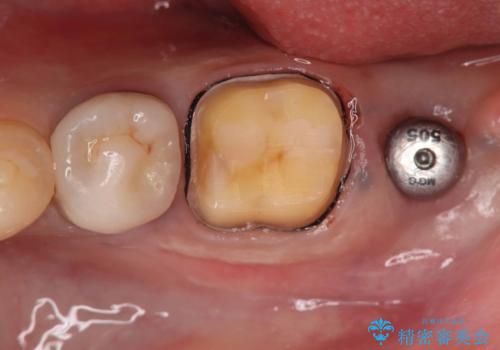

- 過去にヘミセクションが行われていたと思われる左下7番は、大きな歯根嚢胞および根尖病変が認められ、さらに骨縁下カリエスを伴っており、歯肉には瘻孔が形成されている状態でした。

保存は困難と判断し、左下7番は抜歯即時インプラントによる治療を行いました。

抜歯と同時にインプラントを埋入するため、歯茎を切開する必要がなく、術後の痛みが出にくい治療方法です。